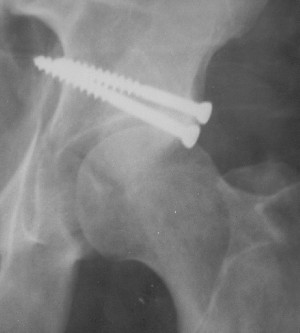

Контрольный снимок перед разрешением нагрузки прямой 13/10/03

Перед разрешением нагрузки боковой 13/10/03

Больной 18 мая 2003 года в автоаварии получил перелом левой вертлужной впадины, вывих бедра. Госпитализирован в один из стационаров области.Вывих вправлен. В последствии бедро вывихивалось еще дважды. На консультацию был представлен снимок от 19.05.03г., больной переведен к нам 3.06.03г. Снимок при поступлении - перелом впадины, задне-верхний вывих бедра. 05.06.2003 г. выполнено открытое вправление вывиха левого бедра и остеосинтез стенки вертлужной впадины двумя винтами. Послеоперационный период без осложнений. Объем движений в левом тазобедренном суставе восстановился полностью. Выписан на амбулаторное лечение в удовлетворительном состоянии с рекомендациями 3 месяца ходить на костылях без нагрузки на оперированную конечность. На контрольных рентгенограммах левого тазобедренного сустава 13.10.2003 г. - признаки консолидации перелома; плотность, форма головки и состояние суставных поверхностей удовлетворительные. Разрешена дозированная осевая нагрузка, на конечность с использованием дополнительной опоры. 19.12.2003 г. больной обратился с жалобами на боли в левом тазобедренном суставе. На рентгенограммах левого тазобедренного сустава 19.12.2003 г., 20.02.04г. - асептичекий некроз головки бедра. 5.04.04г. - эндопротез. Сейчас ходит без трости, не хромает. Особенность эндопротезирования - при удалении винтов прослежена линия перелома заднего края впадины и предложено установить чашку несколько меньшего диаметра, чтобы она была покрыта несломанной частью.